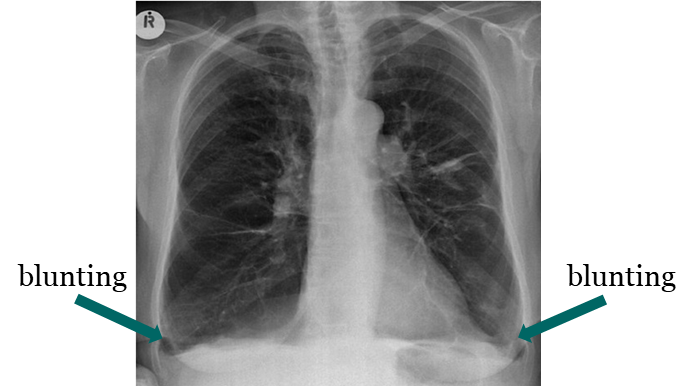

Pleural Effusion

____ is defined as the accumulation of fluid in the pleural space.

____ is seen in the costophrenic angle only (seen on Lat. views), unless it is a high level ___ (Lat. and PA views).

Subpulmonic effusion

____ is an accumulation of fluid between the lung base and diaphragm. It does not blunt the costophrenic angles.